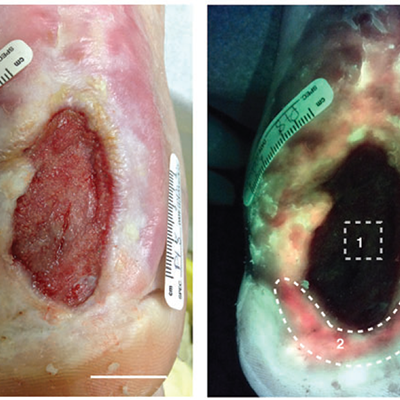

Bacterial fluorescence imaging as a predictor of skin graft integration in burn wounds

Hanson-Viana, E. et al. Burns 2024